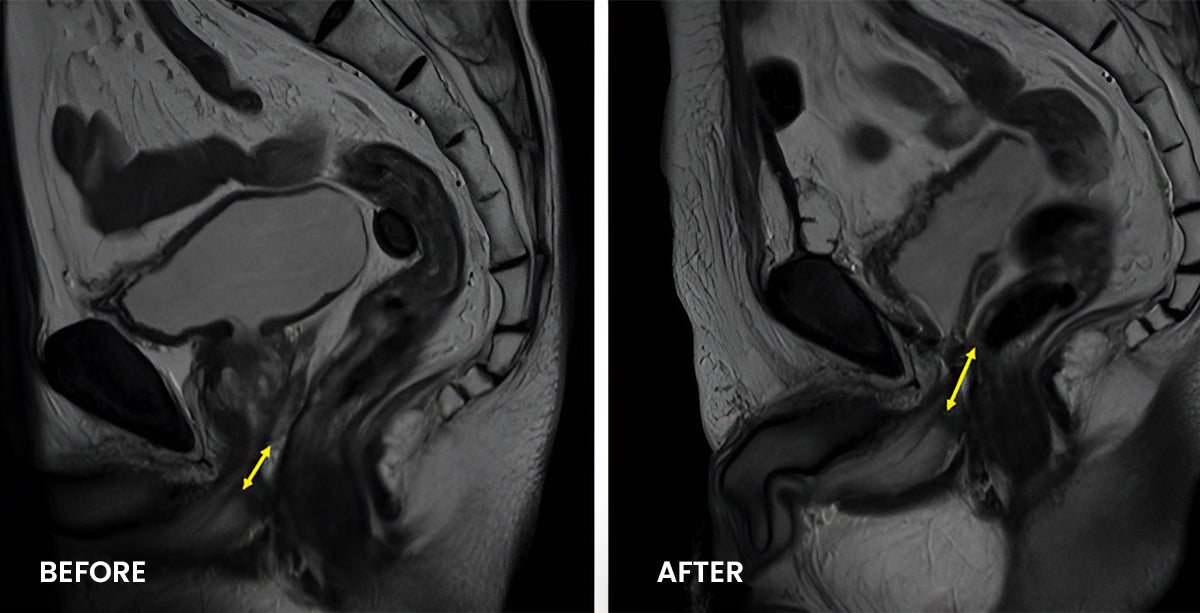

Clinical Research: The Effectiveness of Luhaka™ ProstaMax

Participants in the treatment group reported a significant reduction in Prostate Disease symptoms, including improved urinary flow and decreased frequency of urination.

Participants experienced a notable improvement in urinary function, with increased flow rate and reduced urgency.

Participants reported a reduction in pelvic discomfort and pain, citing an improvement in their quality of life.

Participants noted a marked improvement in overall prostate function, including enhanced erectile function and performance.

*The study noted a decrease in prostate-specific antigen (PSA) levels among participants taking Luhaka™ ProstaMax Prostate Health Support, suggesting a positive impact on overall prostate health.